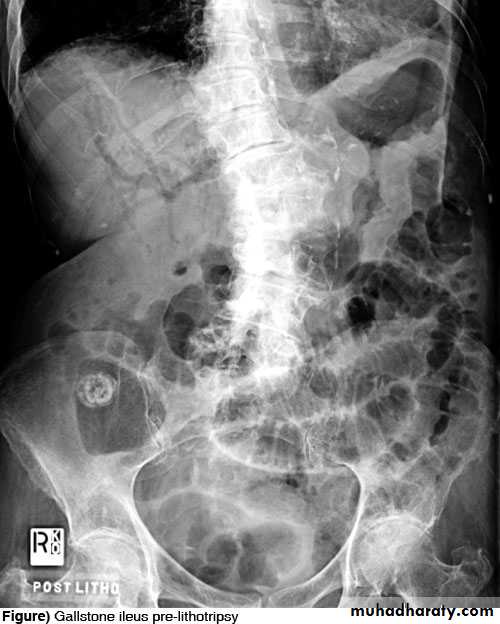

Gallstone ileus

• Gallstone ileus refers to small bowel obstruction secondary to gallstone impaction. Gallstone ileus usually occurs in a setting of chronic cholecystitis where a large gallstone erodes through the inflamed gallbladder wall to enter the duodenum.

• The gallstone then becomes impacted in the distal small bowel causing small bowel obstruction.

• Radiographic signs of gallstone ileus:

• Small bowel obstruction

• Gas in the biliary tree seen as a branching pattern of gas density in the right upper quadrant

• Calcified gallstone lying in an abnormal position is occasionally seen.